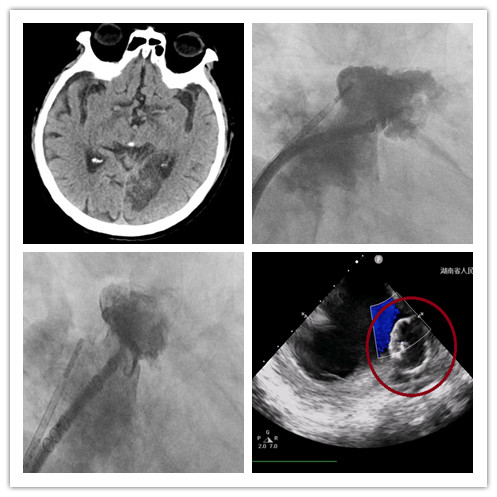

图1、CT显示大面积脑梗死,图2、左心耳造影,图3、左心耳完美封堵,图4、左心耳完美封堵。

和家属商议后,杨嗲嗲转入心内三科,明确脑出血完全吸收后,潘宏伟主任为其实施了经皮左心耳封堵术,在心腔内超声心动图指导下顺利完成左心耳封堵术,从进入到离开手术室不到2小时,整个过程杨嗲嗲没有感受到任何痛苦,感觉自己睡了一觉手术就结束了。